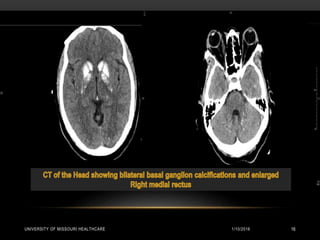

RADIOLOGY

CT Head:

• Scattered hyperdense foci visualized in bilateral basal ganglia and subcortical white

matter of the bilateral occipital lobes and within cerebellum. Right rectus muscle is slightly

more prominent. Findings consistent with Fahr’s disease.

Diffuse calcifications involving all the basal ganglia

1/10/2016UNIVERSITY OF MISSOURIHEALTHCARE 20 Diffuse calcifications involving all the basal ganglia